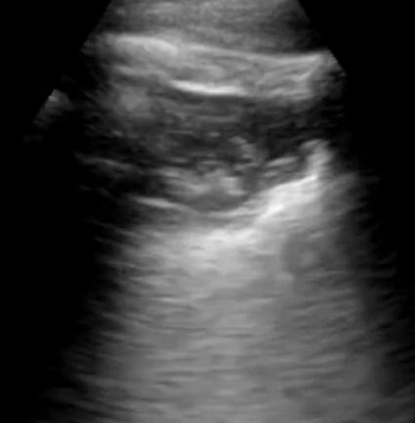

Most deep neural networks (DNNs) based ultrasound (US) medical image analysis models use pretrained backbones (e.g., ImageNet) for better model generalization. However, the domain gap between natural and medical images causes an inevitable performance bottleneck. To alleviate this problem, an US dataset named US-4 is constructed for direct pretraining on the same domain. It contains over 23,000 images from four US video sub-datasets. To learn robust features from US-4, we propose an US semi-supervised contrastive learning method, named USCL, for pretraining. In order to avoid high similarities between negative pairs as well as mine abundant visual features from limited US videos, USCL adopts a sample pair generation method to enrich the feature involved in a single step of contrastive optimization. Extensive experiments on several downstream tasks show the superiority of USCL pretraining against ImageNet pretraining and other state-of-the-art (SOTA) pretraining approaches. In particular, USCL pretrained backbone achieves fine-tuning accuracy of over 94% on POCUS dataset, which is 10% higher than 84% of the ImageNet pretrained model. The source codes of this work are available at https://github.com/983632847/USCL.

翻译:大部分深心神经网络(DNNS)基于超声波(美国)的超声波医学图像分析模型使用预先训练的脊椎(如图像网络)来进行更好的模型化分析。然而,自然图像和医疗图像之间的领域差距造成了不可避免的性能瓶颈。为了缓解这一问题,为在同一领域直接训练建造了一个名为US-4的美国数据集。该数据集包含来自四个美国视频子数据集的23 000多张图像。为了从美国-4中学习强健的特征,我们提议了美国半监督的对比学习方法,名为USCL(USCL),用于预培训。为了避免负面对子与有限的美国视频中丰富的地雷视觉特征之间的高度相似性,USCL采用了一种样品配对生成方法来丰富单步对比性优化所涉及的特征。关于一些下游任务的广泛实验显示了USCL对图像网络预培训和其他状态艺术预培训方法的优势。特别是,USCLU预先训练的骨架在POCS数据集上实现了94 %的微调精准性精确度,这在图像网络上比84%高10 %/MUSPASTASTASTRAIN premstrain practresmex pract press press rodustrismex sramduction sramduction sramduction sramduction surgles)。